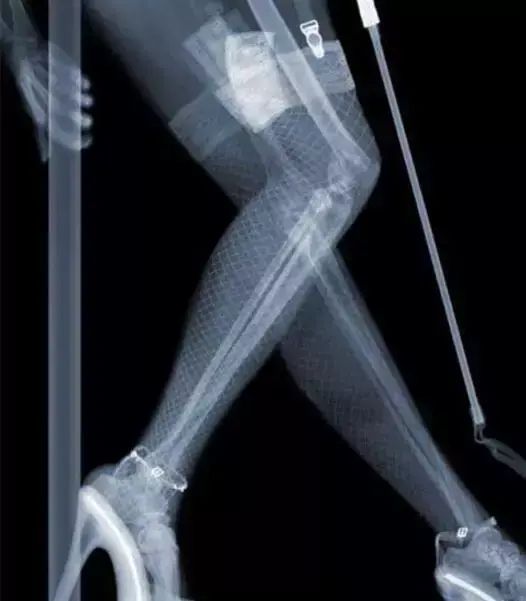

能够直接透过人体的不同组织和杂乱的物品,但由于物质的密度和厚度不一样,被吸收的程度也不同,最终显像处理后,才能得到不同的影像。

工作人员可以根据这些影像,判断你带的东西,是否为违禁物品。

部分不法分子铤而走险,甚至将枪藏于屁股处,企图蒙混过关,最终都被拦下来,还有乘客带的各种奇葩东西,都能看得清清楚楚。

所以,不要妄想不会被发现,安检可是很严格的,包括你身体的每个部位,都一览无余,就连整容人士身上的金属和硅胶,都能清晰看到。

至于隐私,完全可以放心,只有工作人员能看到,其他人想要靠近仪器屏幕,基本是不可能的。更何况去医院检查,也是运用到X光,只会照射到骨骼,不用担心这个问题。